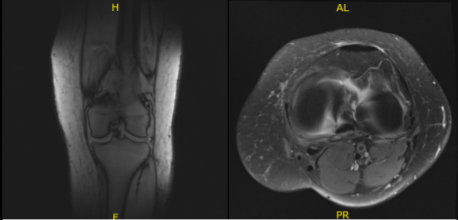

An MRI was done for diagnosis. There is a moderate-sized joint effusion and capsular inflammation. The anterior and posterior cruciate ligaments are intact. There is a complex tear of the body and posterior horn of the medial meniscus. The lateral meniscus is intact.

The quadriceps tendon and patellar tendon are intact. The medial and lateral collateral ligaments are intact. There is moderate patellofemoral chondromalacia with 15 mm partial-thickness erosion involving the medial facet of the patella. No subchondral defect or fracture identified. There is a 10 mm enchondroma in the distal metaphysis of the femur medially.

No osteochondral defect or fracture identified. On the result of the MRI, there was a complex tear of the body and posterior horn of the medial meniscus. Moderate patellofemoral chondromalacia associated with moderate-sized joint effusion and capsular inflammation.

MRI-3T Left Knee Non-contrast